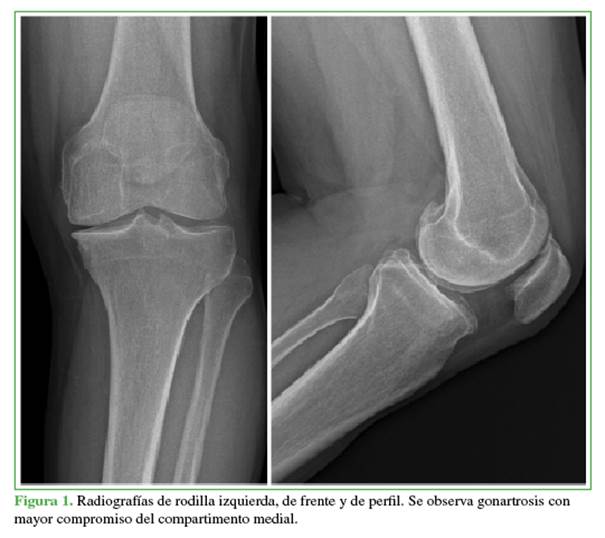

Hombre de 54 años de edad que había sido sometido a una ATR derecha un año atrás, y requirió́ movilizació́n bajo anestesia al mes de la cirugía, en nuestro Centro. Consultó́ inicialmente por gonalgia izquierda severa que lo incapacitaba para sus actividades cotidianas, y que no había respondido al tratamiento conservador durante seis meses. En el examen físico, se observó́ un rango de movilidad de 0° a 100°, sin inestabilidad coronal ni sagital. El dolor preoperatorio según la escala analó́gica visual era 9/10 y el Knee Society Score preoperatorio, 44/60.12 En las radiografías de rodilla de frente y de perfil, se diagnosticó́ genu varo artró́sico (Figura 1).